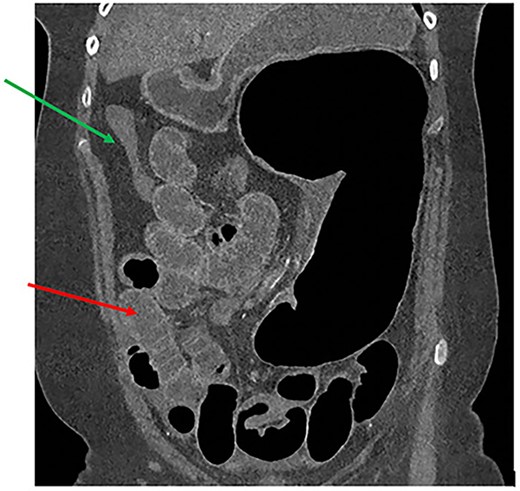

A 61-year-old female with known Marfan Syndrome was admitted to the emergency department with 3-day history of abdominal pain, nausea, vomiting and bowels not opening. Past medical history included three previous episodes of Type A aortic dissection, recent aortic root and ascending aorta replacement alongside bioprosthetic aortic valve replacement. She was an ex-smoker and usually independent at home. On presentation, the patient was haemodynamically stable and apyrexial. Biochemical results were unremarkable except for a Lactate dehydrogenase (LDH) of 309 and a C-reactive protein (CRP) of 101. On examination, she had a diffusely tender and distended abdomen, without signs of peritonism. An erect chest X-ray shows left pleural effusion with a dilated aortic root (Fig. 1). A computed tomography (CT) of thorax, abdomen and pelvis was requested, which demonstrated a caecal volvulus with a dilated cecum of 8.8 cm and upstream small bowel dilatation with air fluid levels, and a chronic aortic dissection extending from the ascending thoracic aorta to the common iliac (Figs 2–4). Following consultation between radiologists, cardiothoracic surgeons and general surgeons, she underwent an emergency laparotomy and right hemicolectomy with side-to-side ileocolic anastomosis. Intraoperatively, the caecal volvulus, comprising a dilated ascending colon measuring up to 10 cm, was delivered and resected along with its mesentery. The patient was admitted to the intensive care unit post-operatively for close blood pressure monitoring and control and stepped down to level 3 wards on day-2 post-operation. Her operation was complicated by a small infected wound haematoma thatwas managed with a 5-day course of ciprofloxacin. A CT of the abdomen and pelvis to investigate a rising CRP on day-9 revealed a subcapsular liver haematoma thath was managed conservatively. The patient was discharged 12-days post-operatively. Histology from the resected colon showed evidence of ischaemia in keeping with a closed loop obstruction such as caecal volvulus. There was also an incidental T1 N0 colonic tumour arising from a sessile serrated polyp and two other serrated polyps. A colonoscopy to inspect the remaining colon has been arranged.

CT thorax, abdomen and pelvis coronal view demonstrating a distended, twisted caecum, caecum in the left upper quadrant, small bowel distension (red arrow) and a decompressed ascending colon (green arrow).

Common findings on radiological imaging are include caecal dilatation, ceacal apex in the left upper quadrant (LUQ), small bowel dilatation, absence of gas in distal colon and single air-fluid level, all which are present in our patient’s imaging (Table 1) [7–10].

In our patient, we can also appreciate the Beaking sign as demonstrated in our CT abdomen (Fig. 2). Other CT findings described in literature that are not seen in our patient includes Whirl sign – a tightly twisted mesenteric vessel and colon.